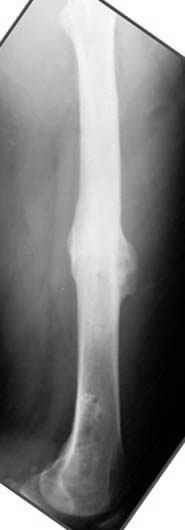

пластическая модель; и коррекция бедра аппаратом Илизарова.

хотя даже если бы и инфекция , то nail exchange с рассверливанием канала - вариант дебрайдмента) Я думаю, что последовательность развития событий:

Узкий к-м канал - тонкий гвоздь- усталостный перелом дистальных винтов - развитие нестабильности и как ее результат остеолиз вокруг гвоздя - деформация анатомической оси бедра. Похоже, что я понял почему аппарат, а не новый гвоздь:-)

ЕТ - Изначально костно-мозговой канал бедра был узкий, дальнейшее его рассверливание ещё больше скомпрометирует прочность бедра( латеральный кортекс дистального отломка уже истончен), приведет к дефекту наружной стенки - хотя это только мои догадки - хотелось бы знать мнение Джолдаса о выбранной тактике.